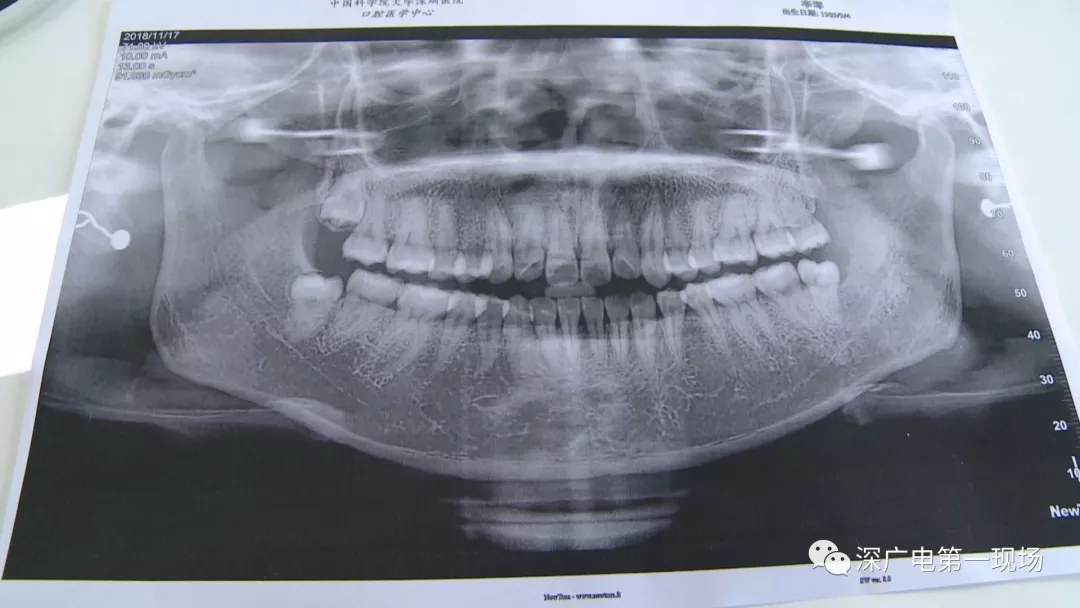

拔一顆智齒一千六?! 深圳這位女士默默的放下了賬單……

隨后,李女士在網(wǎng)上查詢,發(fā)現(xiàn)拔智齒的收費(fèi)都是參差不齊,也沒有參考標(biāo)準(zhǔn)。在李女士提供的拔牙收費(fèi)單上,記者注意到,除了一些拔牙必用的藥物外,還有一些輔助工具的費(fèi)用。

中國(guó)科學(xué)院大學(xué)深圳醫(yī)院口腔科主任賈岳介紹,對(duì)于不同患者的牙齒,它的治療方法都不一樣,所以不同牙齒,醫(yī)院收費(fèi)的標(biāo)準(zhǔn)也各不相同。牙齒的治療方案,都是根據(jù)患者牙齒具體情況來制定,然后再去收費(fèi),同時(shí)也會(huì)參考病人實(shí)際情況來做不同的治療項(xiàng)目。